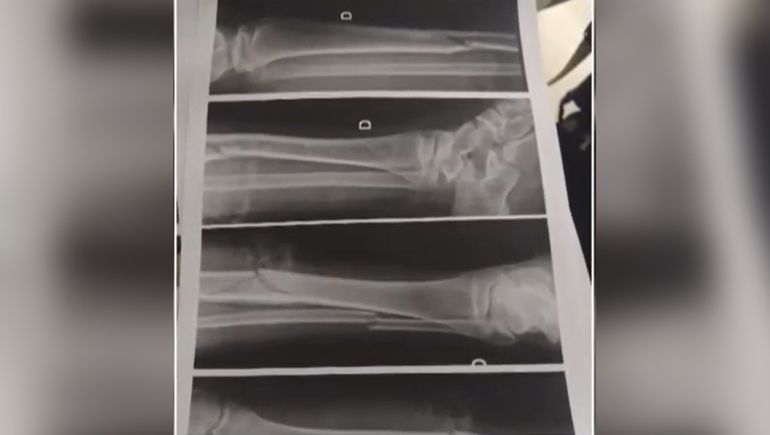

El adolescente lo único que pudo distinguir fue que se trataba de un vehículo grande, tipo Ford 150, de color gris plomo, "es una camioneta grande". “Es una camioneta bien grande, por el espejo retrovisor que dejó. Porque aparte de que le hizo una fractura expuesta en la pierna –tibia y peroné- lo chocó en el hombro con un espejo que quedó en el lugar del siniestro”, precisó.